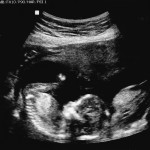

Categories events It’s a Girl! 16 Week Ultrasounds Post author By sean Post date September 7, 2012 Second set of ultrasounds, to help narrow the due date. At an estimated 16 weeks, we now know we are going to have a girl! Tags girl, ultrasounds